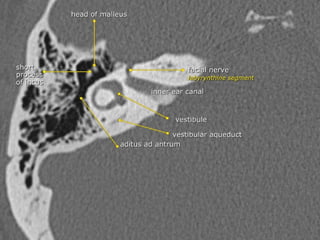

• At the fundus, a transverse crest (crista falciformis) divides the IAC into

superior and inferior compartments

1-Facial nerve (anterior superior) : CN VII (“7 up”)

2-Cochlear part (anterior inferior) : CN VIII (“Coke down”)

3-Superior vestibular nerve (posterior) with superior and

inferior divisions : CN VIII

4-Inferior vestibular nerve (posterior) : CN VIII

• All structures anterior to it are cochlear

• Posterior to it are vestibular